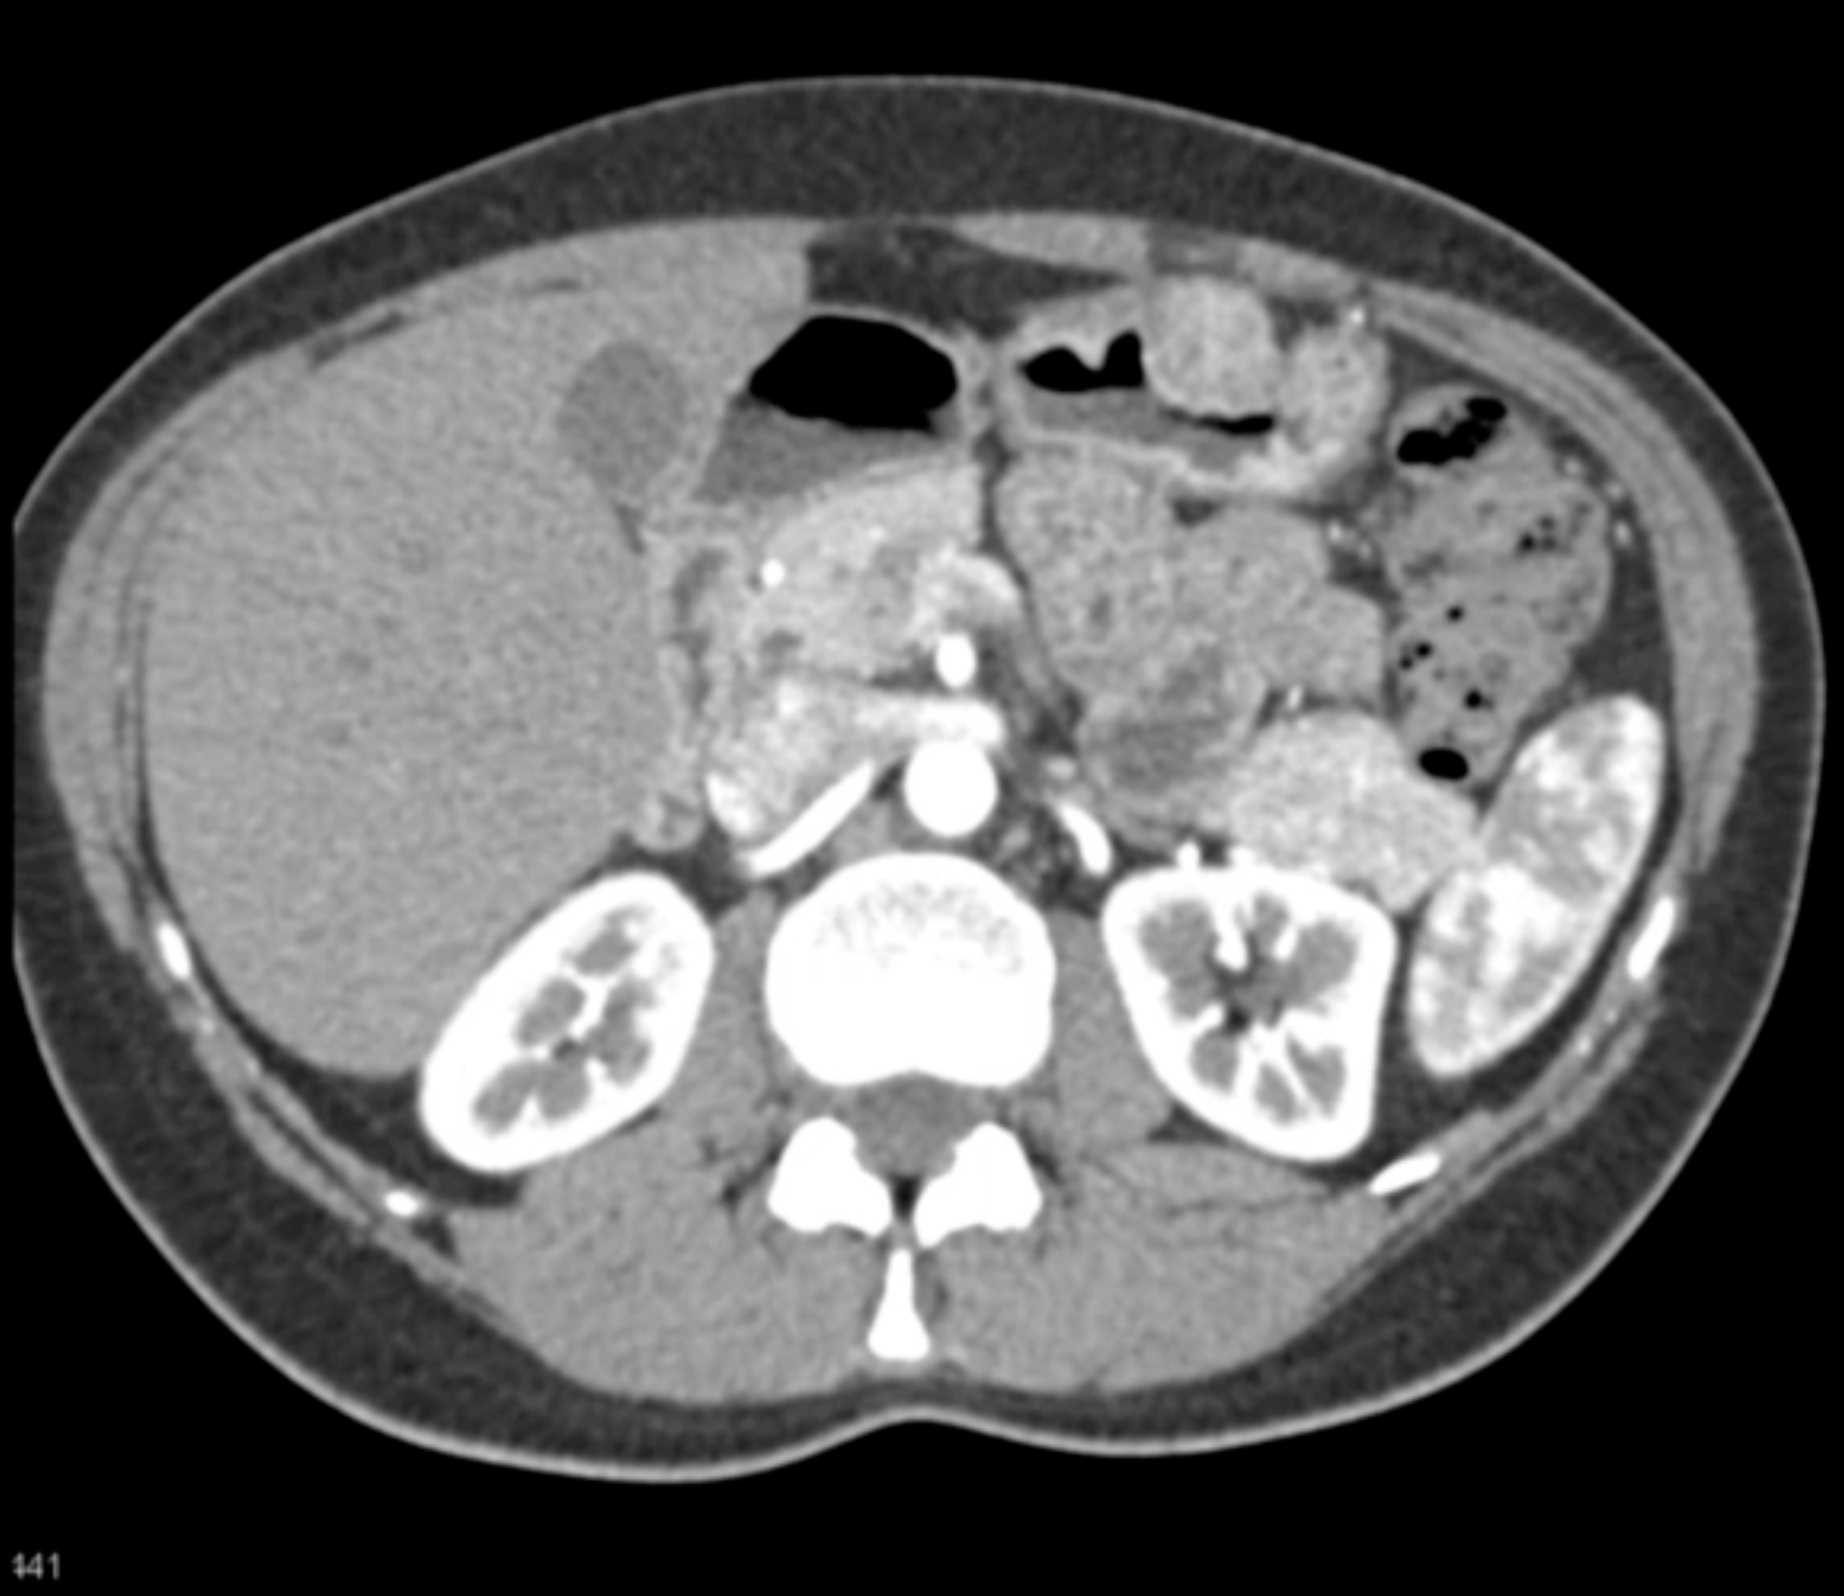

Multiple Gastric GIST Tumors with Spread to Nodes (Carney-Stratakis Syndrome)